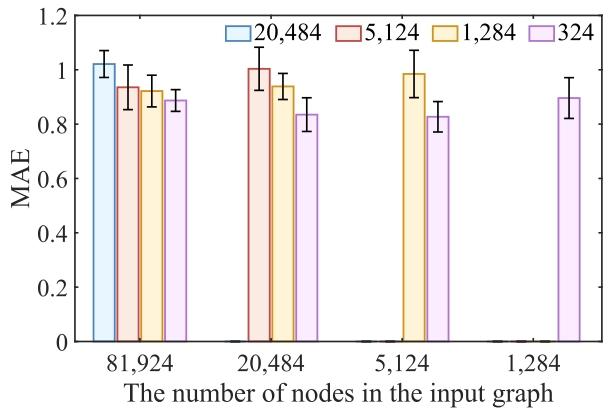

Fig. 3. The scatter plot of the predicted brain ages and postmenstrual ages onthe two cohorts with each input sparse graph consisting of 5124 nodes. R: thecorrelation coefficient between the two axes for each cohort

图 3 输入为 5124 个节点的稀疏图时,两个队列中预测脑龄与月经后年龄(PMA)的散点图